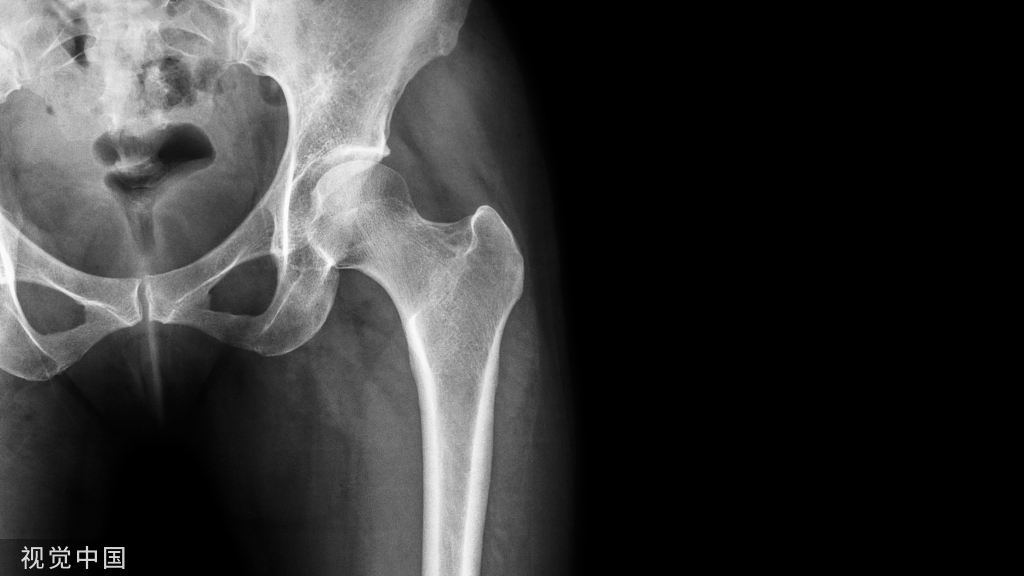

下肢机械力线

1、最佳:中立位(0°)

2、可接受:内外翻≤ 3°

3、术前拍摄下肢全长片,确定股骨外翻角度,以便术中准确行股骨远端截骨(截骨厚度:9~11mm)

4、胫骨近端截骨面垂直胫骨机械轴(截骨厚度:10mm)

5、 冠状面机械力线的确定几无争议